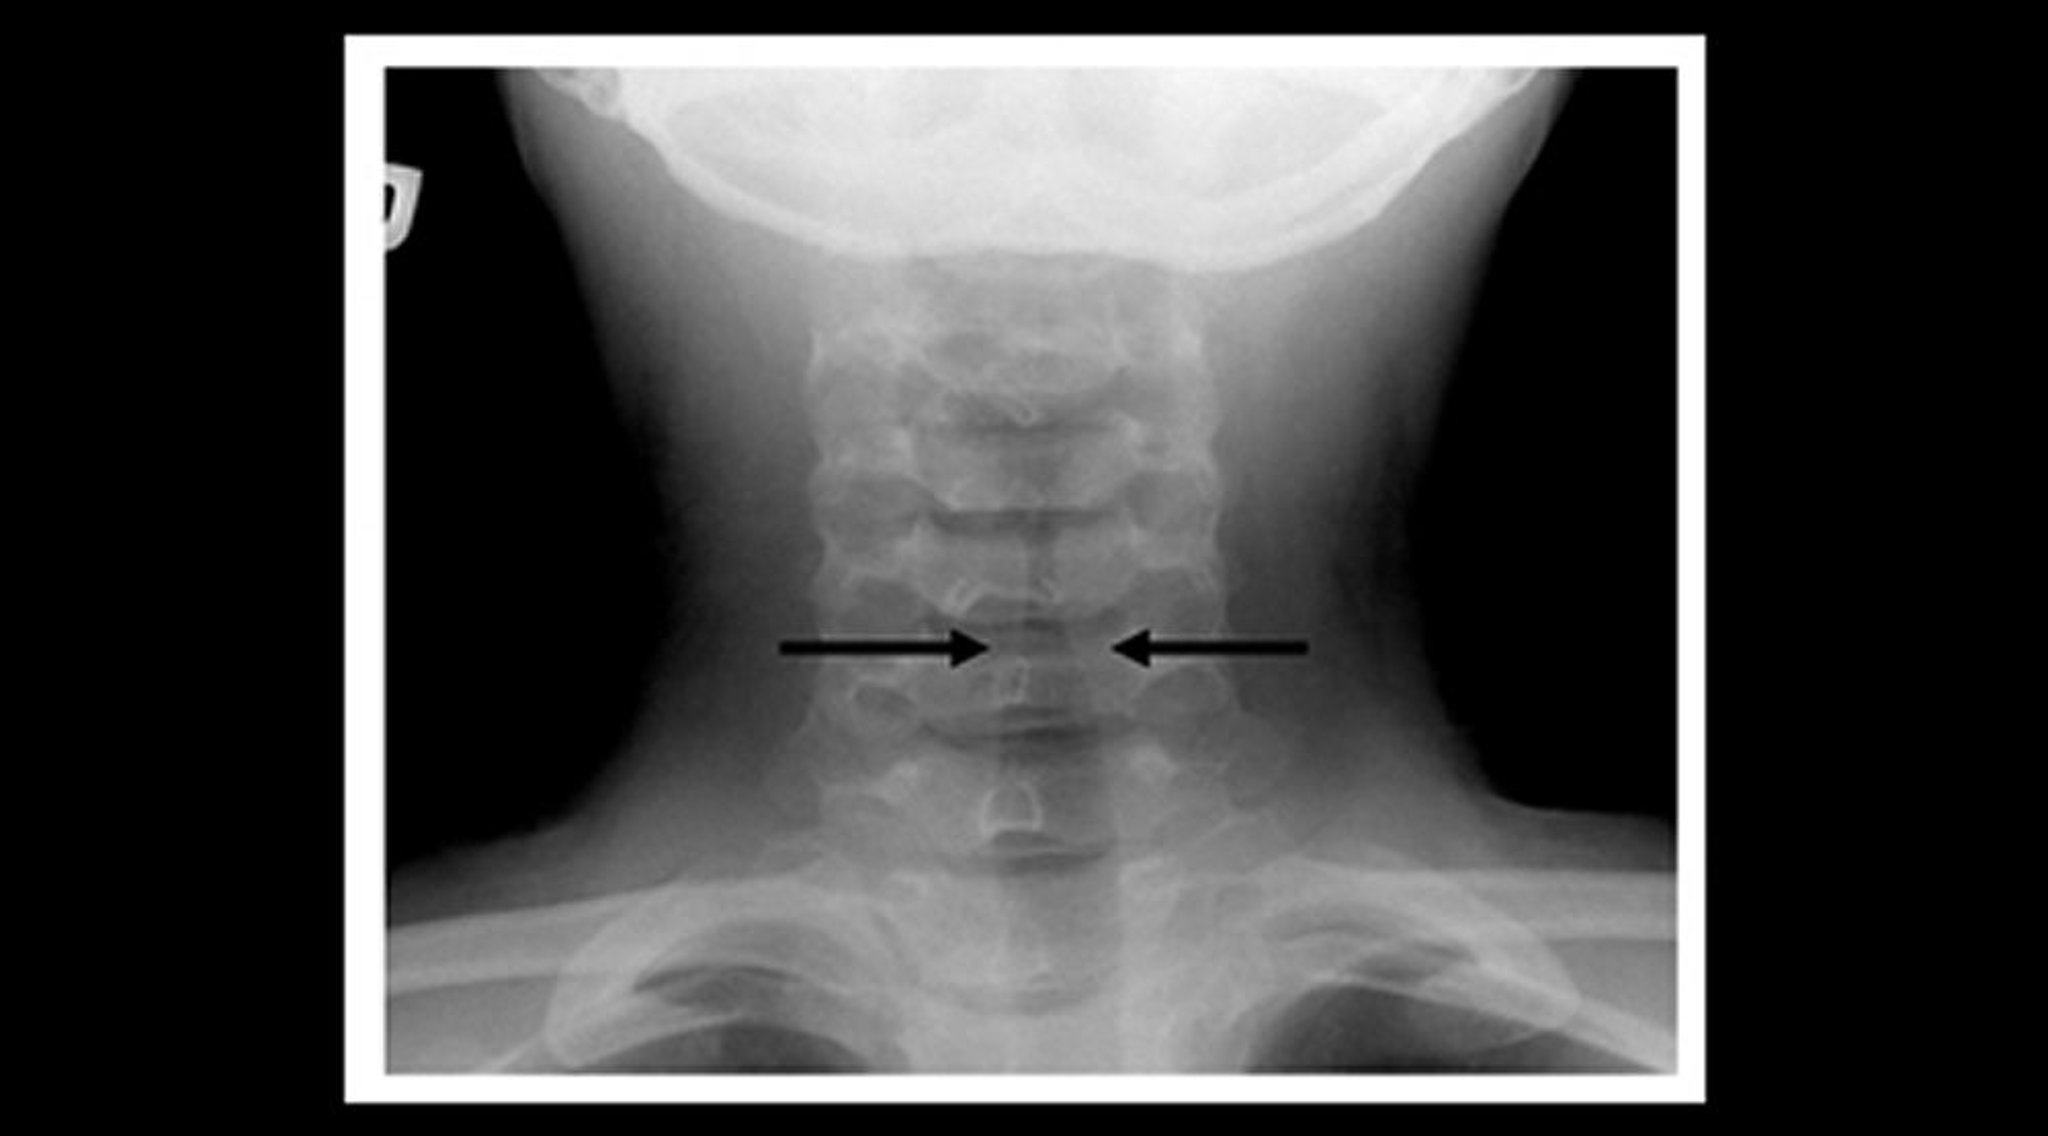

Если диагноз неясен, пациентам нужно провести передне-задний и боковой рентгены шеи и груди; субэпиглоттическое сужение (знак шпиля), выявляемое на передне-заднем рентгене шеи, подтверждает диагноз. Тяжелобольные пациенты с эпиглоттитом должны быть осмотрены в операционной соответствующим специалистом, способным установить поражение дыхательных путей (см. Лечение эпиглоттита). Пациентам необходимо проводить пульсоксиметрию, а тем, у кого имеется респираторный дистресс, можно измерять уровень газов в артериальной крови.

• Диагноз, как правило, ставится на основании клинических данных, но если в передне-задней проекции рентгенограммы шеи и грудной клетки видно классическое сужение подскладочного пространства гортани (симптом шпиля), то это подтверждает диагноз.